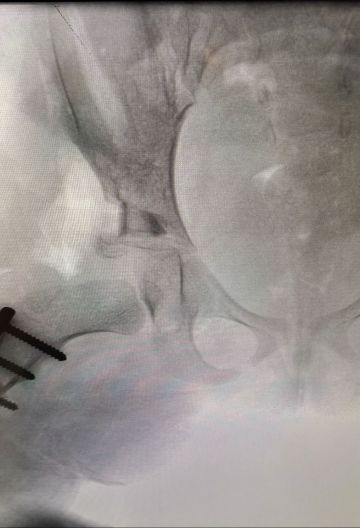

في إنجاز طبي لافت، نجح فريق طبي من قسم جراحة العظام في مستشفى المانع بالخبر، بقيادة استشاري جراحة عظام الأطفال الدكتور إبراهيم البراهيم، في إجراء عملية دقيقة لطفلة تبلغ من العمر أربع سنوات كانت تعاني من خلع ولادي مزدوج في مفصل الورك وتشوه في رأس عظمة الفخذ مع انحراف في عنق العظمة بالجهتين.

وأوضح الفريق الطبي أن هذا النوع من العمليات يُجرى عادة في عمر السنة، ما يجعل نجاحها في هذا العمر المتأخر إنجازًا طبيًا يُحسب للمستشفى وللكادر الجراحي بفضل خبرتهم وكفاءتهم العالية.

وأكدت إدارة المستشفى أن العملية تكللت بالنجاح الكامل، حيث استعادت الطفلة عافيتها بفضل التنسيق المتكامل بين أقسام جراحة العظام والتخدير والتمريض.